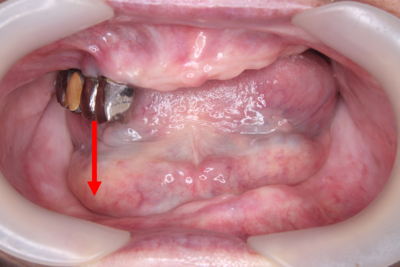

入れ歯装着時のお口の写真

入れ歯を装着した状態を診てみると上あごと下あごの入れ歯には隙間が見えます。つまりあまり噛んでないということが分かります。向かって右側は、正常な噛み合わせですが、向かって左側は、若干、噛み合わせがズレています。

上あごと下あごの正中が合っていません(写真:赤線と青線)。ということは噛み合わせも合っていないということになります。患者さまの顎がズレているのか、入れ歯の排列した歯がズレているのか、またはその両方なのかを考えながら作る必要があります。